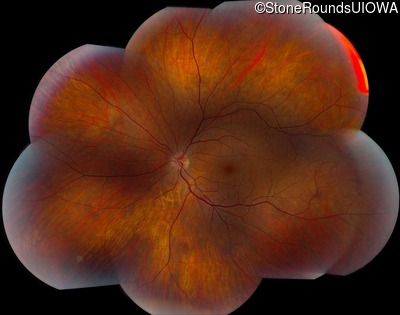

AD CSNB (IA2fii)

AD CSNB (IA2fii)

History

This 44 year old woman has had very poor vision in dim light for her entire life. She vividly remembers running into a picnic table on a bicycle in a campground as a child.